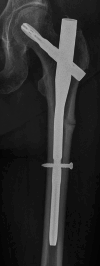

Background: Austria is among the countries with the highest incidence and prevalence of osteoporotic fractures worldwide. Guidelines for the prevention and management of osteoporosis were first published in 2010 under the auspices of the then Federation of Austrian Social Security Institutions and updated in 2017. The present comprehensively updated guidelines of the Austrian Society for Bone and Mineral Research are aimed at physicians of all specialties as well as decision makers and institutions in the Austrian healthcare system. The aim of these guidelines is to strengthen and improve the quality of medical care of patients with osteoporosis and osteoporotic fractures in Austria.

Results: The guidelines include all aspects associated with osteoporosis and osteoporotic fractures, such as secondary causes, prevention, diagnosis, estimation of the 10-year fracture risk using FRAX®, determination of Austria-specific FRAX®-based intervention thresholds, drug-based and non-drug-based treatment options and treatment monitoring. Recommendations for the office-based setting and decision makers and institutions in the Austrian healthcare system consider structured care models and options for osteoporosis-specific screening.